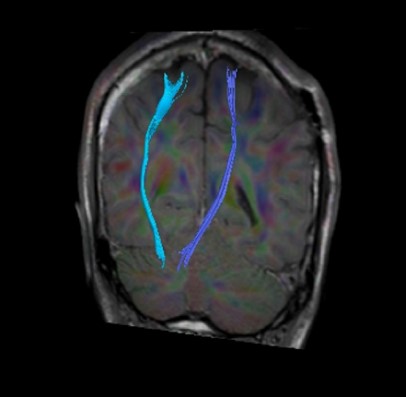

トラクトグラフィ

トラクトグラフィとは白質神経線維の走行方向を可視化したものです。脳神経外科の術前評価に役立ちます。

カラーマップ トラクトグラフィ